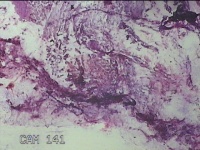

左侧输卵管系膜囊肿

性别

女

年龄

41岁

临床诊断

子宫肌壁间肌瘤

一般病史

发现子宫肌瘤4年余。

标本名称

大体所见

灰白色圆柱形条索状组织10.5x7x1.3㎝一堆,切面均为灰白色结节状或编织状,质硬。